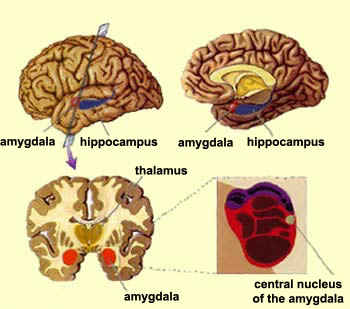

Amygdala: What It Is and What It Controls

Know Your Brain: Amygdala

Damage to the Amygdala: Functions, Symptoms, & Treatments

Amygdala Function and Location

Limbic System: Amygdala (Section 4, Chapter 6) Neuroscience Online

Amygdala's Location and Function

Amygdala - The Science of Psychotherapy

Amygdala: Anatomy, Location, and Function

Schematic drawing illustrating the location of the amygdala and